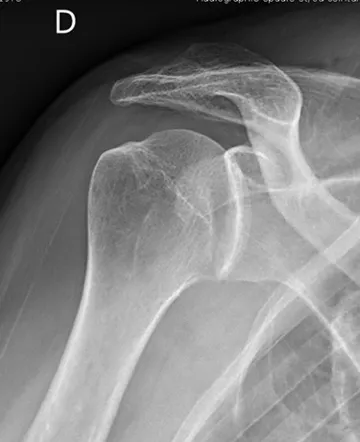

- Radiographies — bilan de débrouillage, recherche de lésions osseuses associées

Les lésions osseuses

- Fracture du rebord glénoïdien — la tête humérale heurte violemment la glène et en arrache un fragment. Quand cette perte osseuse est importante, les techniques arthroscopiques seules ne suffisent plus.

- Encoche de Hill-Sachs — la tête humérale s'écrase contre la glène comme une balle de ping-pong qu'on écraserait avec le doigt. Cette déformation est irréversible.